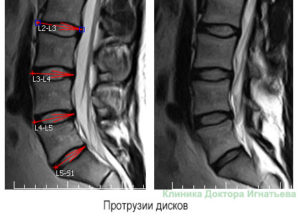

- Протрузию – грыжевое выпячивание не превышает 3 мм.

- Пролапс – выпячивание составляет 3-5 мм, в этой стадии могут развиваться клинические симптомы заболевания.

- Развитая грыжа – выбухание диска составляет более 6 мм. При этом часто фиброзное кольцо разрывается, студенистое ядро выходит наружу, формируется секвестрация диска.

По степени выпячивания

- Протрузии – выпячивания до 3 мм.

- Пролапс – фиброзное кольцо выходит за пределы позвонка в рамках 3-5 мм.

- Развитые грыжи, когда разрывается оболочка диска.

Протрузия диска — 1 стадия формирования грыжи межпозвоночного диска, во время которой происходит повреждение внутренних волокон фиброзного кольца без разрыва внешней оболочки, которая удерживает студенистое ядро в своих границах, образуют подвижный фрагмент.